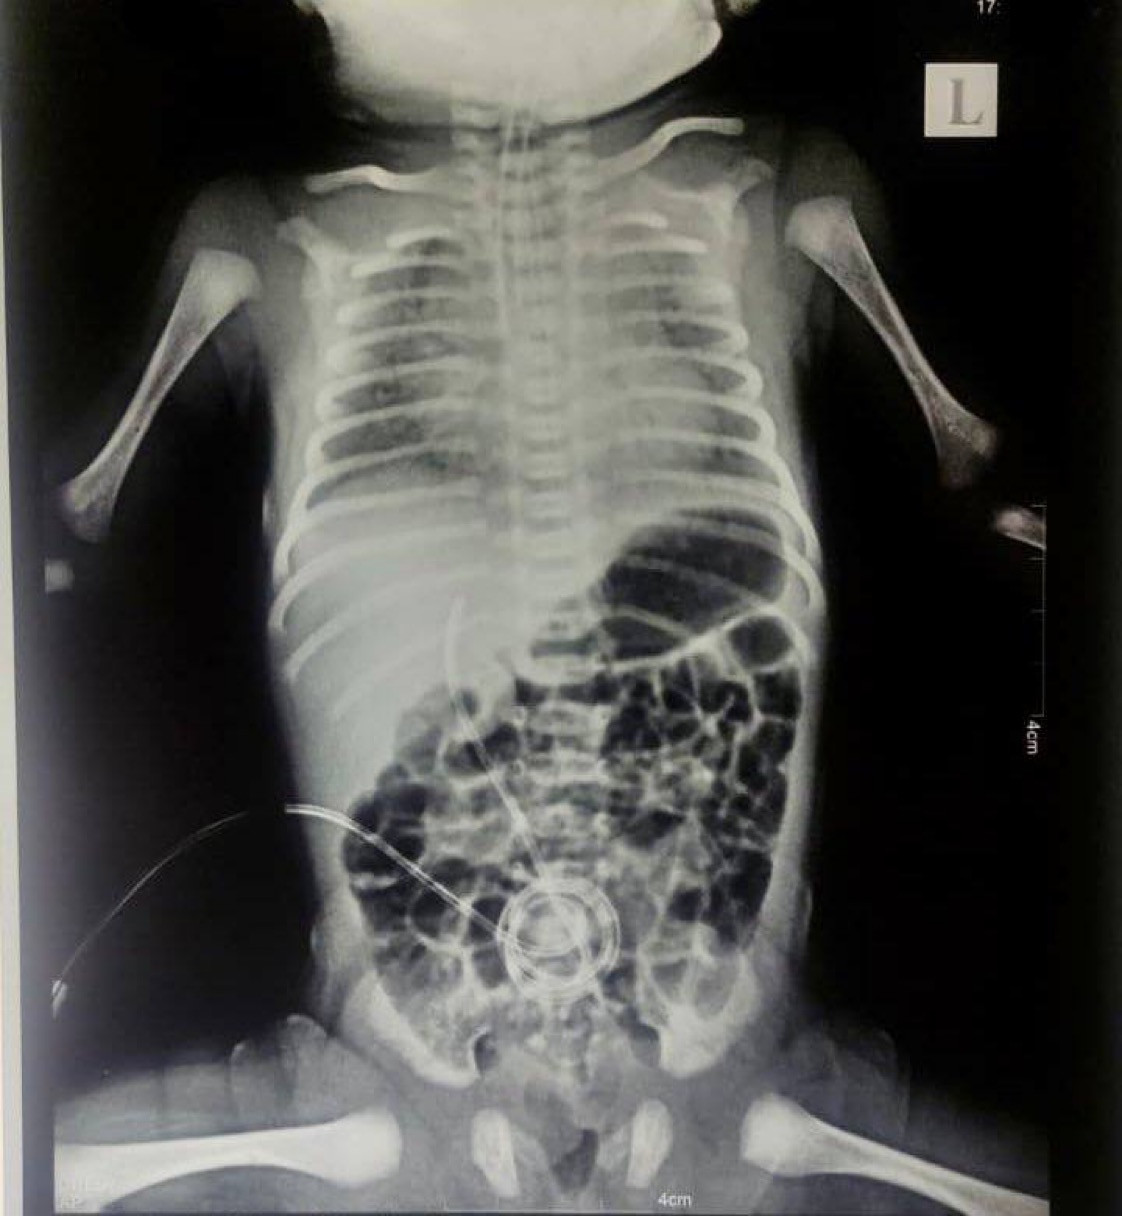

"Fully Vaccinated Mother’s Dying Newborn With White Lungs. A pattern of Multisystem Inflammatory Syndrome in Neonates"

“We have a dying infant with MIS-N, born to a vaccinated mother who never had any symptoms of Covid, and no positive test, and yet the doctors are blaming Covid!”

Newborn diagnosed with Multisystem Inflammatory Syndrome in Neonates, MIS-N

•Uneventful pregnancy, up to the point when the baby is born, revealing dysfunctional lungs, infant unable to breathe on their own, and the newborn ends up being hooked up to the highest throughput ventilator."